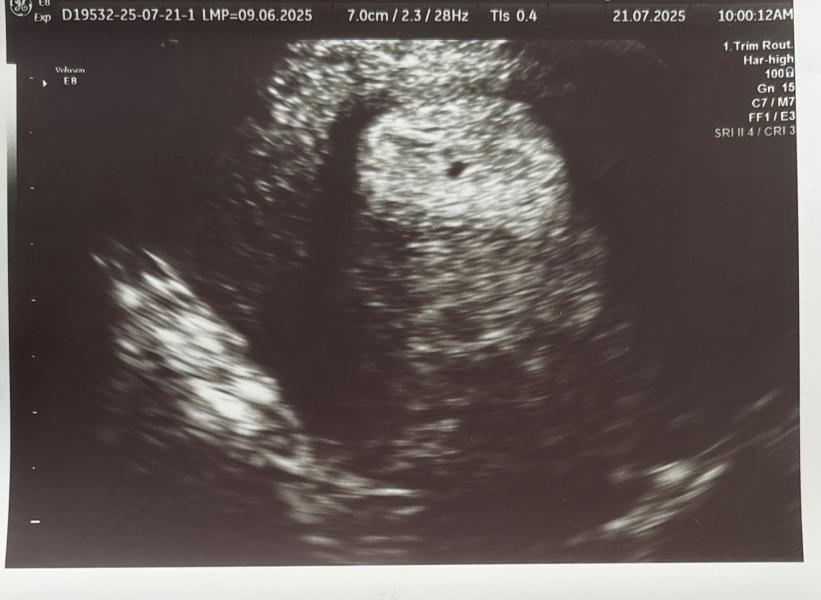

21 июля отправилась на УЗИ в клинику «Под сердцем». Так как акушерский срок 6 недель, думала, что получится уже послушать сердцебиение, но мы еле-еле увидели плодное яйцо. Оно есть, оно в матке, но очень маленькое, не соответствует сроку. Заключение по узи прикрепляю. По словам врача показалось, что все не очень хорошо. Она назначила пересдать ХГЧ и через неделю повторно прийти на УЗИ. Понимаю, что возможна поздняя овуляция и имплантация, но теряю надежду на хорошее, очень плохо морально. У кого-то были похожие ситуации?